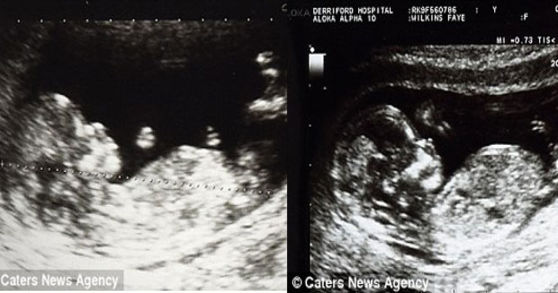

Faye Wilkins İngilterede Plymouth şehrinde yaşayan 31 yaşında ve iki çocuk sahibi bir anne… Çift vajina ve çift rahim boynuna sahiptir. Bununla beraber iki tane rahme sahiptir. Senelerdir doktora gidip anne olamayacağını söylediler. 31 yaşına kadar 6 kez düşük yaptı fakat Faye Wilkins yılmadı. Pes etmeyen Faye Wilkins, sonunda hamile kaldı ve şimdi biri 7 yaşında biri de 2 yaşında olan mucizevi çocukları dünyaya getirdi. Çocuklarının ismini ise Molly ve George koydu. Bu mucizevi durumunu anne Wilkins paylaşmak istedi ve sosyal medyadan iki rahme sahip olduğunu ve iki çocuğunun birini sol birini sağ rahminden doğurduğunu açıkladı.

Tıp dilinde Uterus Didelphys olan çift rahim anlamına gelen bu teşhis, çok az kadında görülüyor. Nadir görülen bu duruma sahip olan Faye Anne doğumdan sonra “Neyse ki şimdi iki küçük mucizeye sahibim… Sağlıklı doğdukları için çok mutluyum” dedi. İlk bebeği olan Molly’i sol rahminden hamile kaldığını açıklayan Faye Wilkins ikinci bebeği olan George ise sağ rahminden hamile kaldığını açıkladı.